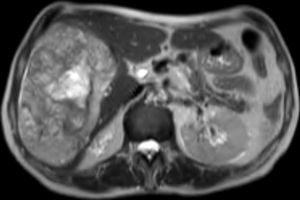

The patient was assessed by the Interventional Radiology Department of our hospital. Abdominal ultrasound showed that there was no intra-abdominal free fluid. At this time, the possibility of performing arteriography and embolization of the right hepatic artery was ruled out due to that fact that the intratumoral bleeding was from the right portal branch. The patient was taken to surgery, where we carried out an extended right subcostal laparotomy and observed a large tumor mass that occupied the entire right liver lobe from the right dome of the diaphragm to the pelvis, which was elastic in consistency and violet in color (Fig. 2). We performed right hepatectomy under total vascular exclusion. The patient was discharged on the 8th day post-surgery with no complications. In the pathology study of the surgical specimen, a neoplastic proliferation of epithelioid or fusiform cells was observed with atypia that formed nests or vascular structures interspersed with areas of hemorrhage and necrosis, showing cellular uptake with vascular markers (CD31, CD34, F.VIII), compatible with high-grade angiosarcoma (Fig. 3).

The microscopic study of the surgical specimen reveals a neoplastic proliferation of epithelioid cells with atypia forming nests or vascular structures interspersed with areas of hemorrhage and necrosis, showing cellular uptake with vascular markers (CD31, CD34, F.VIII), compatible with high-grade angiosarcoma.